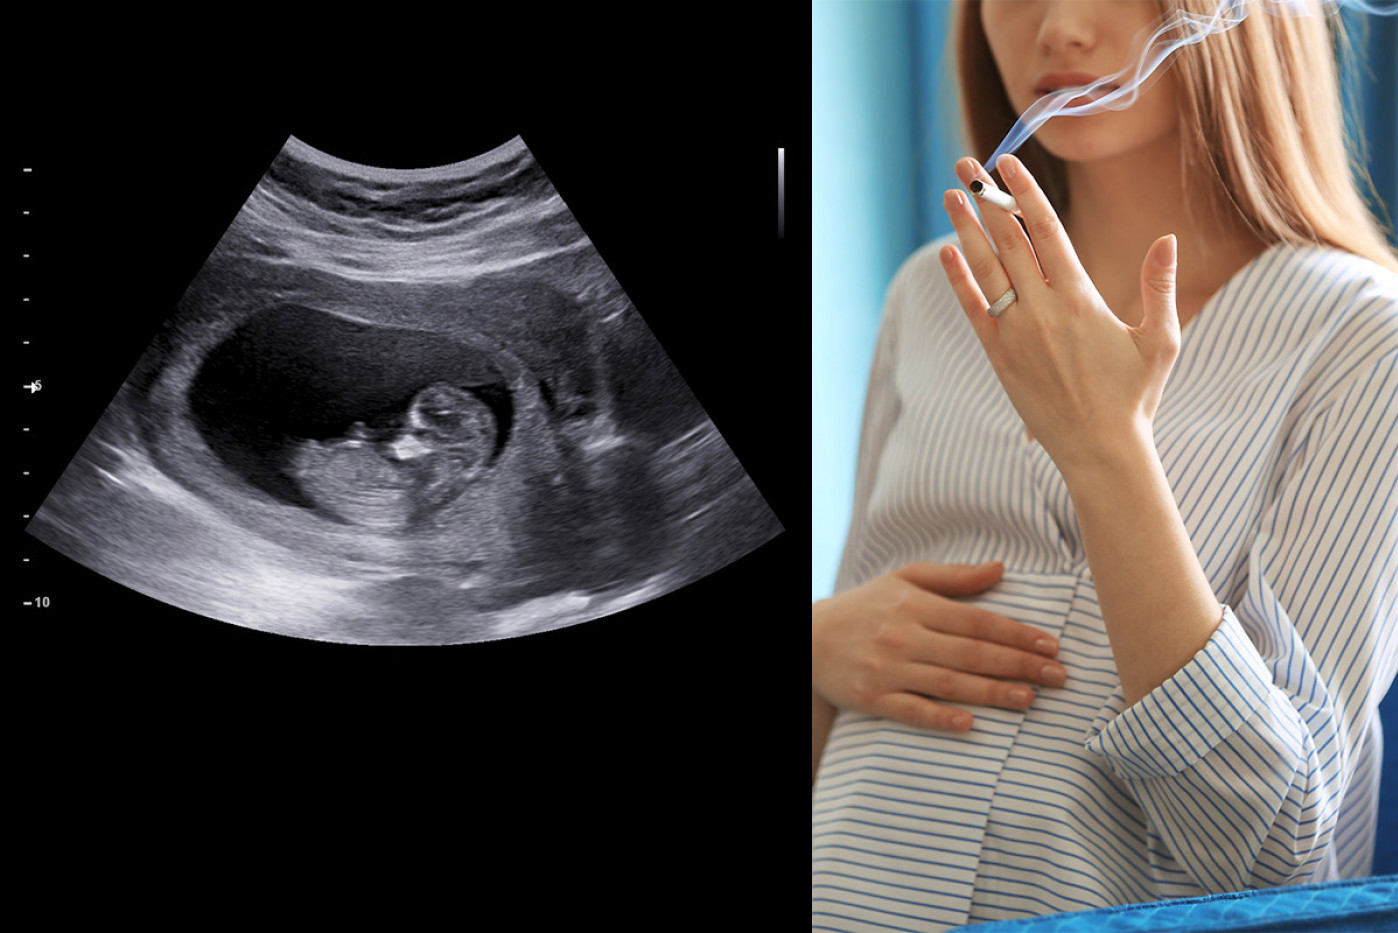

Snimci ultrazvučnih pregleda privukli su pažnju širom sveta, jer su pružili uvid u to kako izgledaju bebe u stomaku kada majka puši. Ovaj fenomen je postao predmet studija istraživača sa Univerziteta u Darhamu i Univerziteta u Lančesteru, koji su odlučili da uporede snimke ultrazvuka beba čije su majke pušile tokom trudnoće sa onima čije majke to nisu radile.

Tokom istraživanja analizirano je 80 ultrazvučnih snimaka beba nastalih između 24. i 36. nedelje trudnoće. Od ukupnog broja snimaka 16 beba imalo je majke koje nisu pušile tokom trudnoće, dok su majke četiri bebe pušile u proseku 14 cigareta dnevno. Rezultati su bili zapanjujući.

Uočeno je da su bebe čije su majke pušile tokom trudnoće pokazivale određene karakteristike na ultrazvučnim snimcima koje nisu imale bebe čije su majke bile nepušači. Ovo je izazvalo zabrinutost među stručnjacima i javnošću, naglašavajući ozbiljne posledice pušenja tokom trudnoće.

Istraživanje sprovedeno na bebama čije su majke pušile tokom trudnoće pokazalo je zanimljive rezultate. Naime, snimci su otkrili da su ove bebe često prekrivale lica i pomerale usta, što ukazuje na značajno veći nivo pokretanja usana u odnosu na prosečnu bebu. Ovo je izazvalo zabrinutost među istraživačima jer sugeriše da nervni sistem beba čije su majke pušile možda nije razvijen na isti način kao kod beba čije su majke izbegavale pušenje tokom trudnoće.

Autorka istraživanja ističe da zaključak izveden iz ovih rezultata upućuje na to da izloženost nikotinu ima veći uticaj na razvoj fetusa, nego izloženost stresu i depresiji.